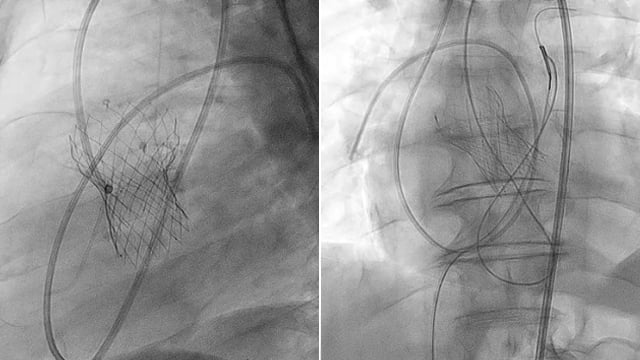

Management of patient with complex left main stenosis - LIVE case

14 May 2024 – From EuroPCR 2024

A 52-year-old male, with a history of STEMI treated by PPCI on RCA one month ago, presents with angina CCS 2 and severe, calcified stenosis in the LAD, CX, and distal left main. The treatment involved implanting 2 stents in the LAD after Rota preparation, followed...